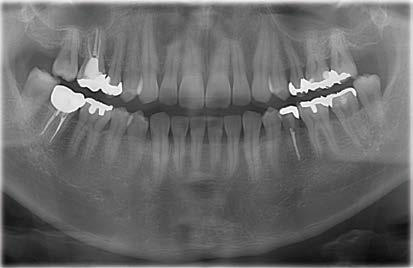

Klinisches Fallbeispiel

Die Panoramaaufnahme zeigt einen horizontal impaktierten Eckzahn im linken Unterkiefer. Eine weitere Untersuchung einer 3D-Aufnahme ergibt einen Zusammenhang zwischen dem impaktierten Zahn und den vorderen unteren Schneidezähnen. Ferner lässt sich ein Zahnsäckchen erkennen, was auf eine vorhandene Dentitionszyste hindeutet.